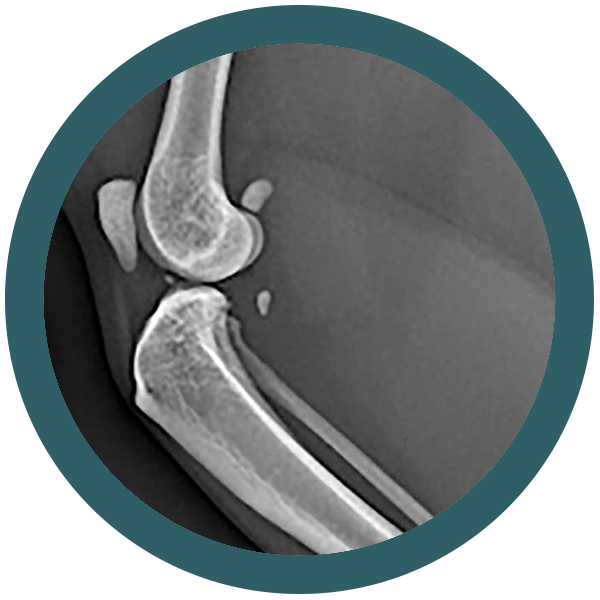

Come riconoscere una displasia dell’anca nel gatto

Osteocondrodisplasia Scottish Fold: quando la dolcezza delle orecchie nasconde un problema serio